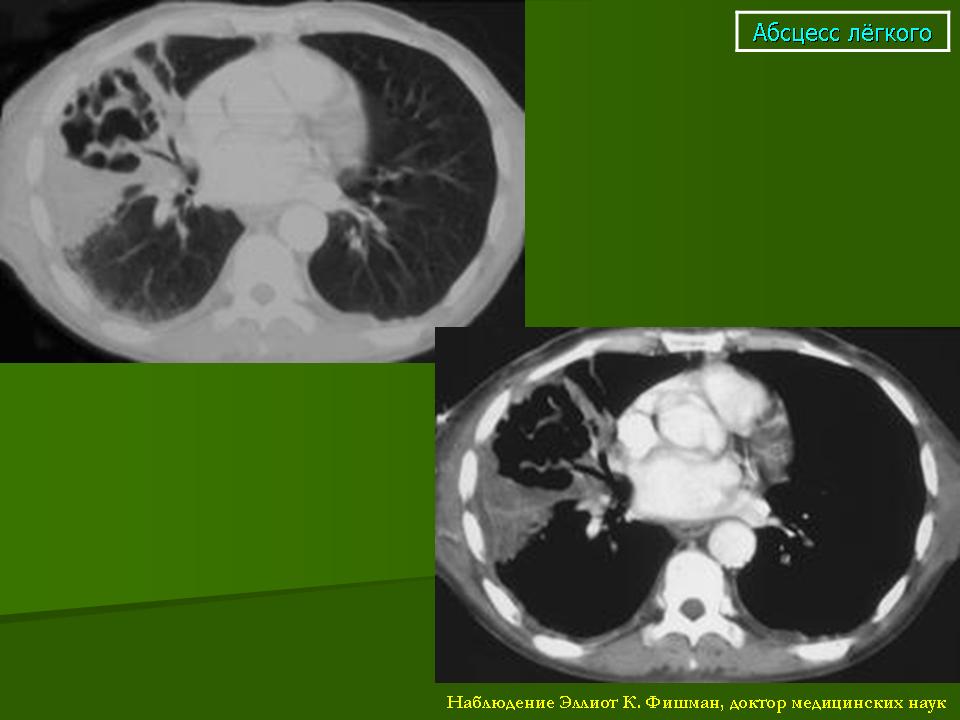

КТ диагностика тубоовариального абсцесса: Подходы и изображения